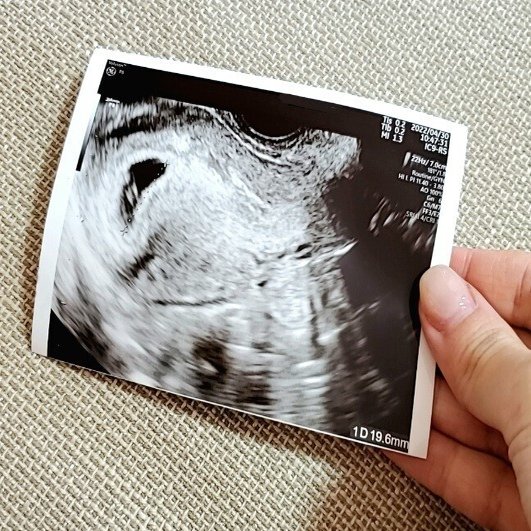

ちなみに初めてのエコー写真がこちら。

左上に写っている小さいのが胎嚢

この時点でおよそ5w5d

先生からエコー写真を渡された時、これが噂のエコー写真か!とドキドキしながら受け取った時の気持ちをまだ覚えています。

思ってたよりペラペラで薄かった(笑)

エコー写真って何年が経つと消えてしまうそうなので、帰宅してすぐ小さめのジップロックに保存しました。

そして旦那が帰宅してから改めてエコー写真を見せながら報告。

まだあまり実感が湧いてない様子でしたが、喜んでくれました(*^^*)